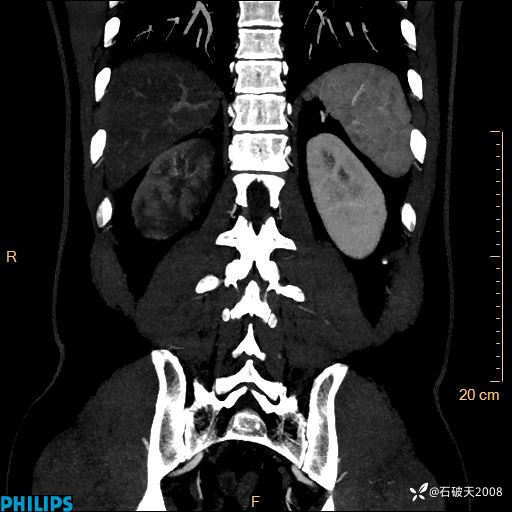

MIP

平扫轴位

增强轴位

冠状位